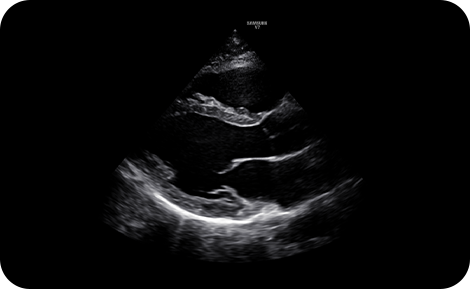

2D PLAX with H armonic

Reduce noise to improve

2D image quality

ClearVision enhances the edge contrast and creates sharp 2D images for optimal diagnostic performance.

precise imaging : ClearVision

2D PLAX zoom mode with ClearVision